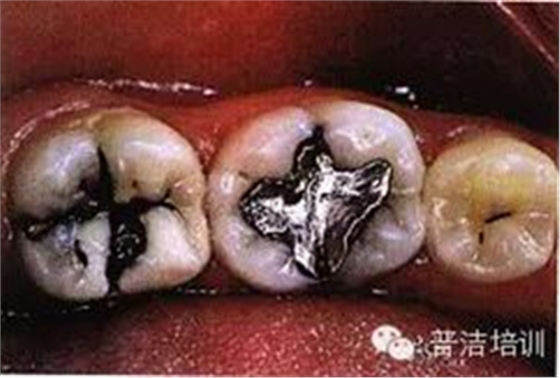

一、下頜后牙牙合面廣泛齲壞,檢查后決定行樹脂嵌體修復(fù)

二、去除齲壞的組織,可以使用送風(fēng)公司生產(chǎn)的齲齒檢測液來判斷齲壞的組織是否去除干凈